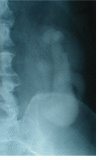

Case presentation: A 51-year male developed incomplete tetraplegia in 1997 when he slipped and fell backwards hitting his head on the floor. X-rays of cervical spine showed fusion at two levels: C2 and C3 vertebrae, and C4 and C5 vertebrae. Intravenous urography (IVU) revealed no kidneys in the renal fossa on both sides, but the presence of crossed, fused renal ectopia in the left ilio-lumbar region. This patient had a similar cervical spinal cord injury about 15 years ago, when he developed transient numbness and paresis of the lower limbs following a fall.

Discussion and conclusion: 1) Persons with Klippel-Feil syndrome should be made aware of the increased risk of sustaining transient neurologic deterioration after minor trauma if there is associated radiographic evidence of spinal stenosis.2) Patients with Klippel-Feil syndrome often have congenital anomalies of the urinary tract. Our patient had crossed, fused, ectopia of kidney.3) When patients with Klippel-Feil syndrome sustain tetraplegia they have increased chances of developing urinary tract calculi. Treatment of kidney stones may pose a challenge because of associated renal anomalies.4) Health professionals caring for cervical spinal cord injury patients with Klippel-Feil syndrome and renal anomalies should place emphasis on prevention of kidney stones. A large fluid intake is recommended for these patients, as a high intake of fluids is still the most powerful and certainly the most economical means of prevention of nephrolithiasis.